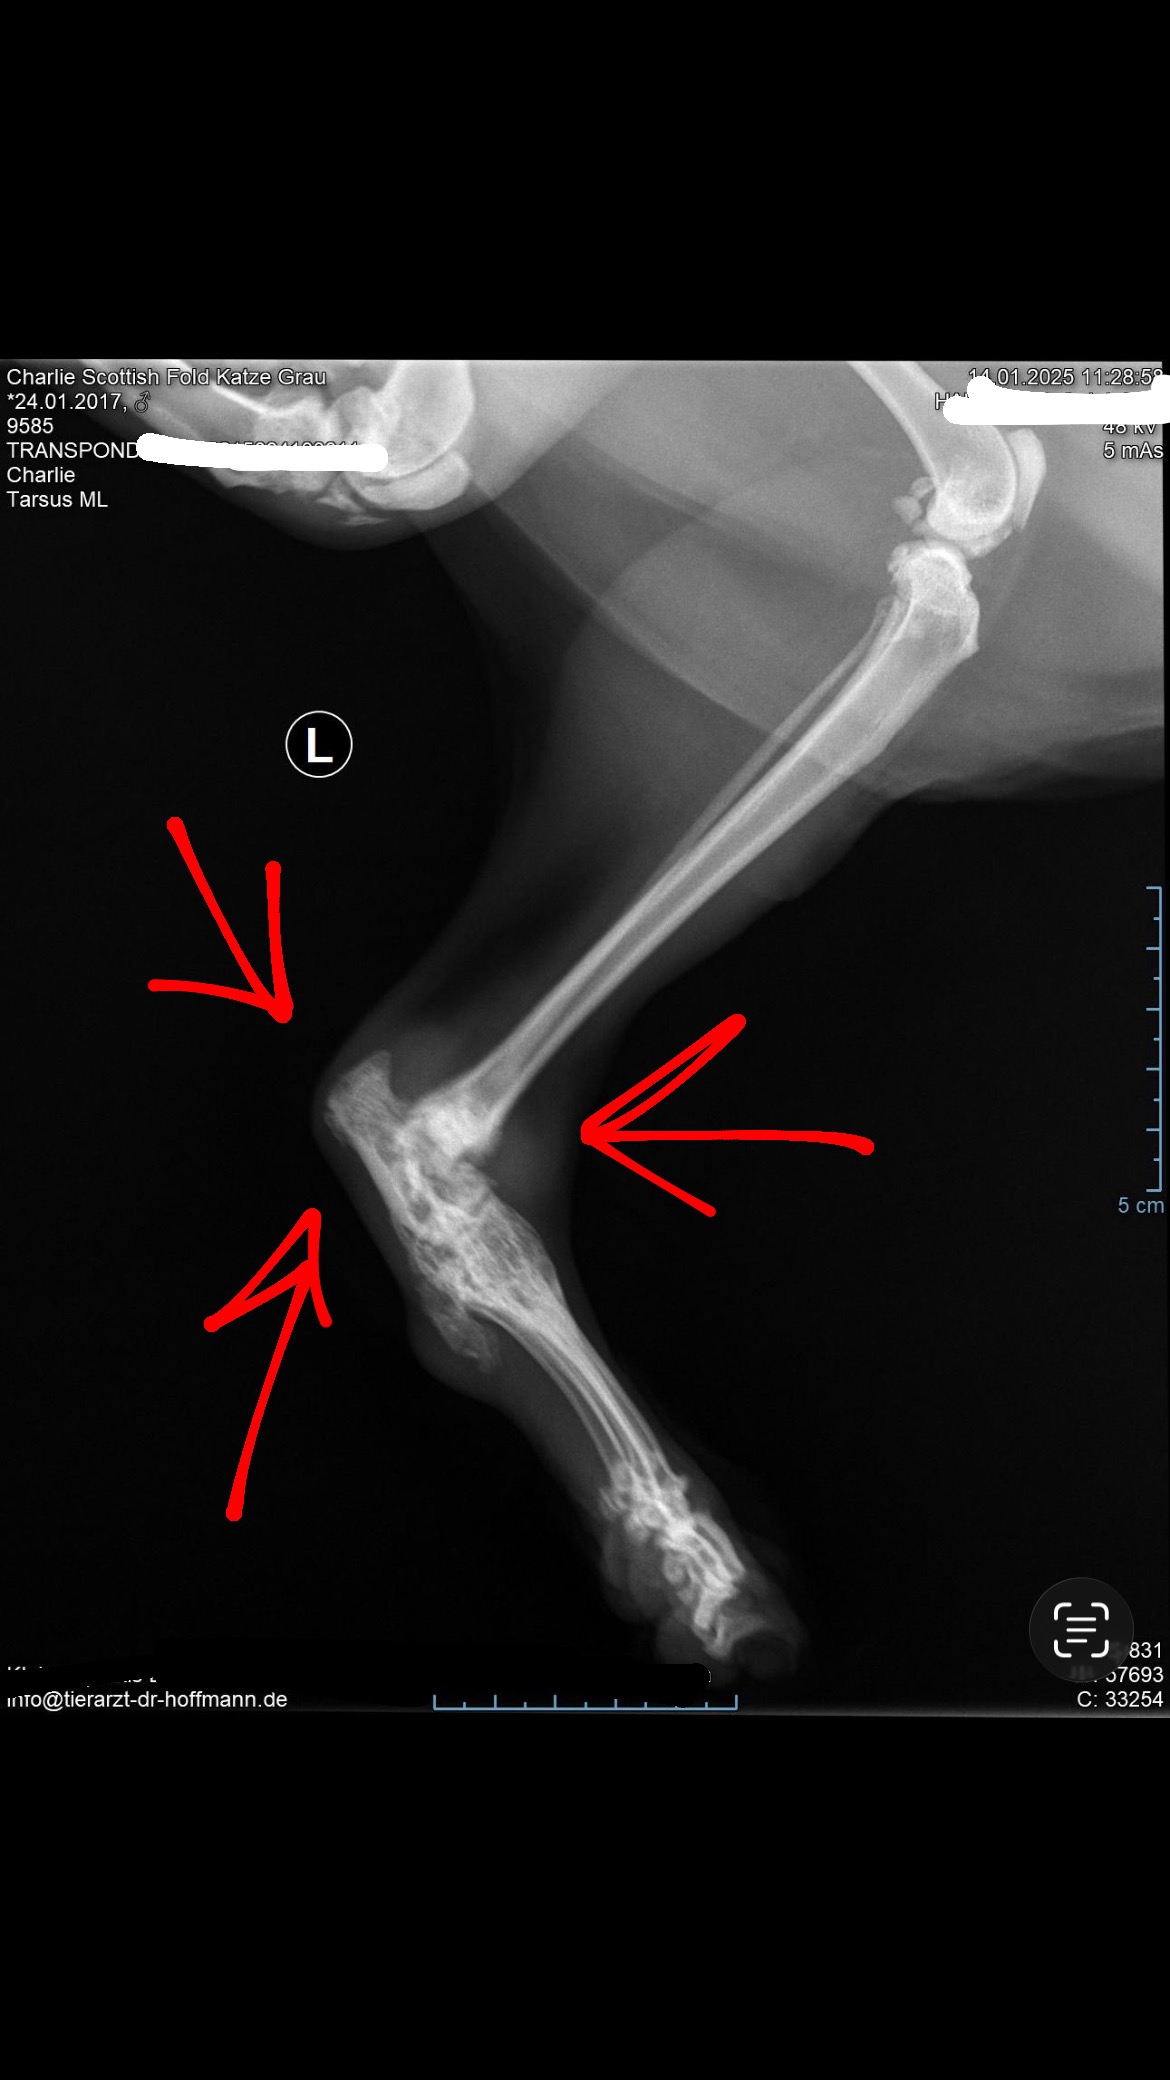

Last year he was diagnosed with Osteoarthritis, which is a chronic painful degenerative joint disease. The cartilage between the bones gradually breaks down and because of this the joints become stiff inflamed and painful. He is a scottish-fold, which gives him a predisposition for this chronic illness.

This makes everyday movements like jumping and running impossible for Charlie anymore. He struggles to walk and when it hurts too much he pulls himself with the front legs.